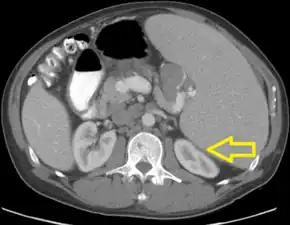

Acute tumor lysis syndrome after proximal splenic artery embolization-CT of abdomen shows splenomegaly with compression of left renal parenchyma arrow

TLS should be suspected in patients with large tumor burden who develop acute kidney failure along with hyperuricemia (> 15 mg/dL) or hyperphosphatemia (> 8 mg/dL). (Most other acute kidney failure occurs with uric acid < 12 mg/dL and phosphate < 6 mg/dL). Acute uric acid nephropathy is associated with little or no urine output. The urinalysis may show uric acid crystals or amorphous urates. The hypersecretion of uric acid can be detected with a high urine uric acid - creatinine ratio > 1.0, compared to a value of 0.6–0.7 for most other causes of acute kidney failure.